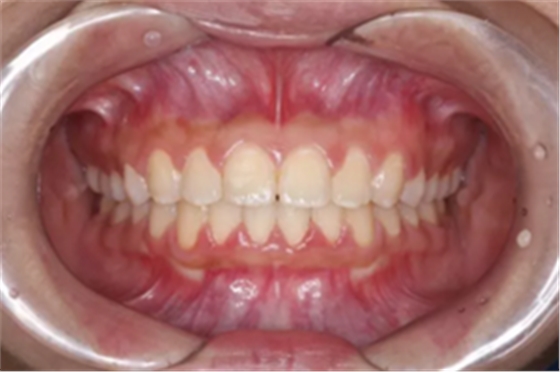

前牙閉鎖合-深覆合

前牙閉鎖合覆蓋